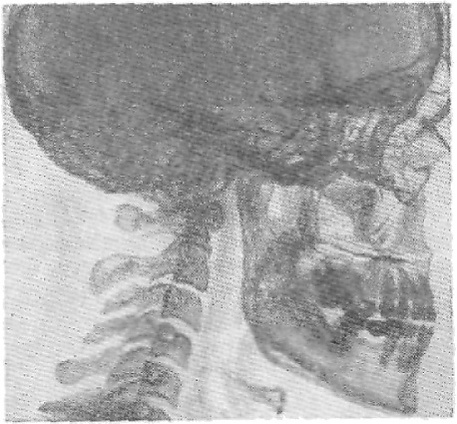

Рентгенодиагностика акромегалии способствует уточнению диагноза. Рекомендуется произвести обзорные снимки черепа в боковой и лобной проекциях и прицельные рентгенограммы турецкого седла. Боковая томограмма, сделанная через срединную сагиттальную плоскость черепа, способствует получению более точной информации о состоянии турецкого седла[5].

Ещё в ранней фазе заболевания, когда отсутствуют выраженные эндокринные расстройства, возникают изменения турецкого седла в виде выпрямления спинки, истончения её основания и склерозирования верхней её части[5].

В выраженных случаях при акромегалии череп большого размера. Особенно увеличен лицевой скелет[5].

Кроме изменений черепа, в выраженных случаях акромегалии на снимках оказываются увеличенными и утолщёнными позвонки. Как правило, увеличиваются кости кистей и стоп. Головки фаланг пальцев обычно утолщены, ногтевые отростки расширены, неровные. Длинные трубчатые кости увеличены, массивны. Бугры и шероховатости костей у мест прикреплений мышц выступают больше, чем в норме[5].